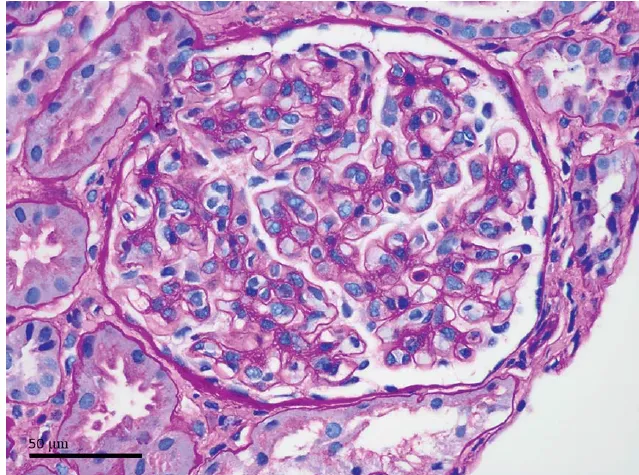

A biópsia do enxerto evidenciou inflamação intersticial significativa com infiltração por eosinófilos e linfócitos, glomerulite severa (g3), capilarite peritubular (ptc3) e contornos duplos na membrana basal glomerular (cg1). A coloração C4d foi positiva, confirmando rejeição mediada por anticorpos crônica ativa rica em eosinófilos.